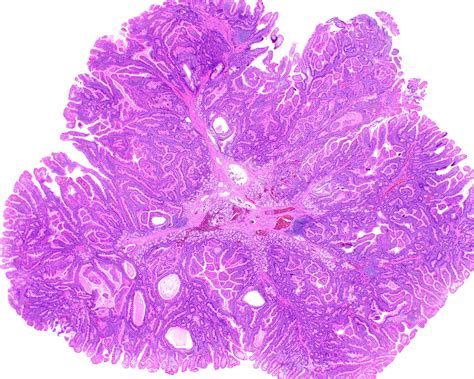

UMiami Pathology (@UMiamiPathology) / Twitter